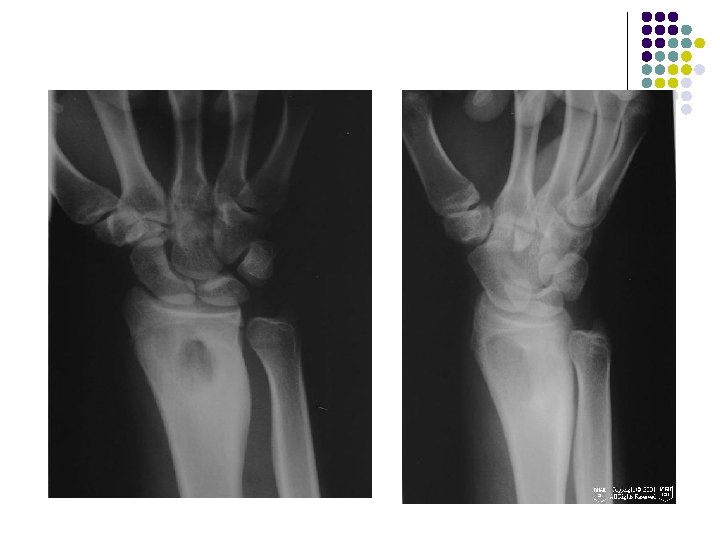

Case - 1 l A young boy of 11 years presented with c/o wrist pain WITHOUT any significant soft tissue swelling.

Radiographic Findings: Wrist Films: l Lobulated lytic lesion of the distal radius abutting the articular surface and extending from the epiphysis into the proximal metaphysis. l matrix calcification are seen. MR: l The lesion demonstrates low signal on T 1 weighted images and high signal on T 2 weighted images with rings and arcs compatible with chondroid matrix. l No extra-osseousoft tissue mass is seen.

Diagnosis l Chondroblastoma

CHONDROBLASTOMA l Age : 5 -25 years l monostotic. COMMON SITES: long bones - femur, humerus, tibia. Arise in an epiphysis May extend into the metaphysis. l l A thin sclerotic rim may separate the tumor from the adjacent normal bone. l Matrix mineralization (60%) typically punctate and less commonly in a pattern of rings and arcs. Periostitis, Soft tissue masses, pathologic fractures are rare. l

AP radiograph of the left wrist shows an expanded solitary lytic lesion involving closed epiphyses subarticular position of the distal ulna without rim of sclerosis or periosteal reaction which is typical for a giant cell tumor

Giant cell tumor of distal radius is eccentric and extend to the end of the bone